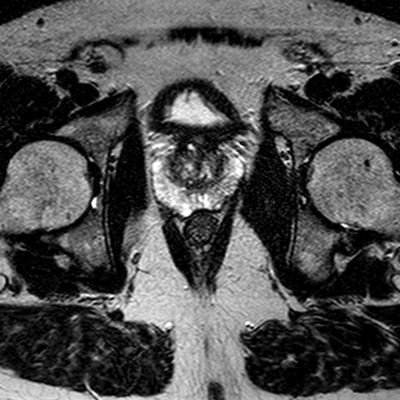

On T2-weighted images, the normal peripheral zone demonstrates homogeneous high signal intensity. The outer margin of the peripheral zone is demarcated by a thin rim of low signal intensity, which represents the true prostate capsule. The neurovascular bundles are low-signal intensity structures seen posterolateral to the true capsule and are surrounded by high-signal fat [4] (Figure 2).

Figure 2: Axial T2 image showing high signal peripheral zone

and low signal capsule and heterogenous central zone.

It is difficult to distinguish the transitional zone from the central zone on MRI, and these are usually described radiologically as a collective ‘central zone.’ The central zone is normally hypo-intense on T2W, although this is variable. Benign conditions such as benign prostatic hyperplasia (BPH) may give a heterogeneous appearance to the central gland with low to intermediate signal intensities. A low-signal intensity rim also surrounds the central zone, often referred to as the surgical pseudocapsule [2]. The vas deferens and seminal vesicles, being fluid-filled structures, normally demonstrate high signal intensity on T2W images.